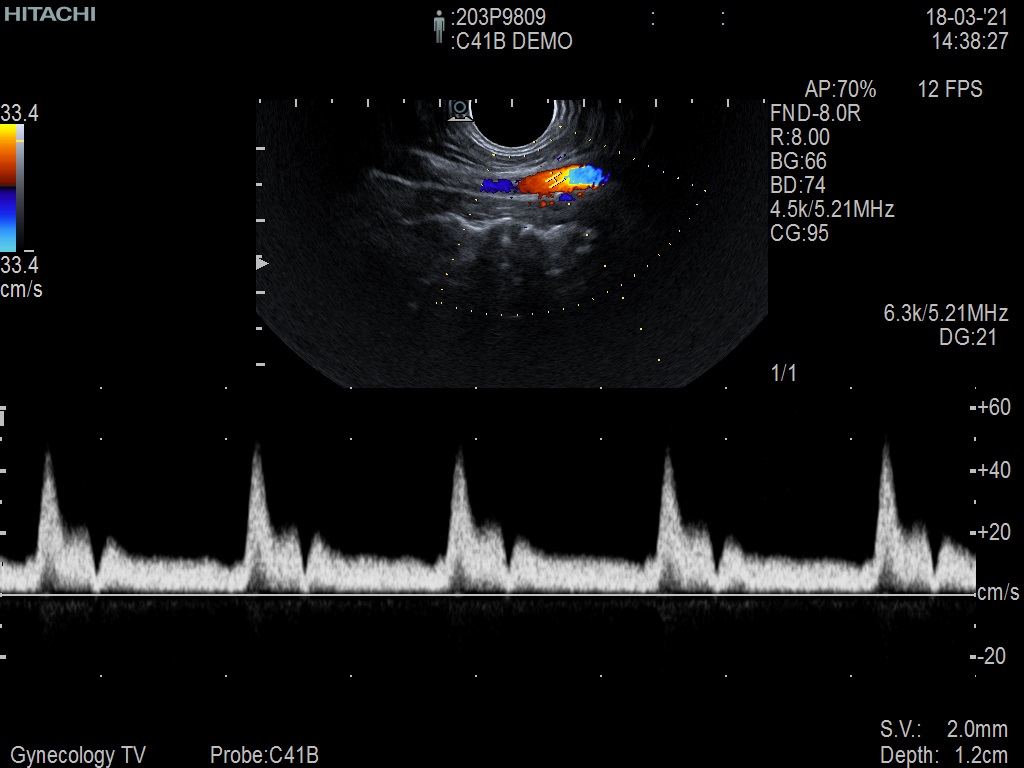

Hitachi C41B DEMO Endocavity Vaginal – ARIETTA

ARIETTA Endocavity C41B

Angled End-fire Endocavity

Hitachi C41B Endocavity Vaginal – ARIETTA

Frequency Range: 10 – 2 MHz

Scan Width: 10 mm Radius

Scan Angle: 200° FOV

Hitachi C41B Endocavity Vaginal/Rectal – ARIETTA for Angled End-fire Obstetric, Gynecology and Endorectal